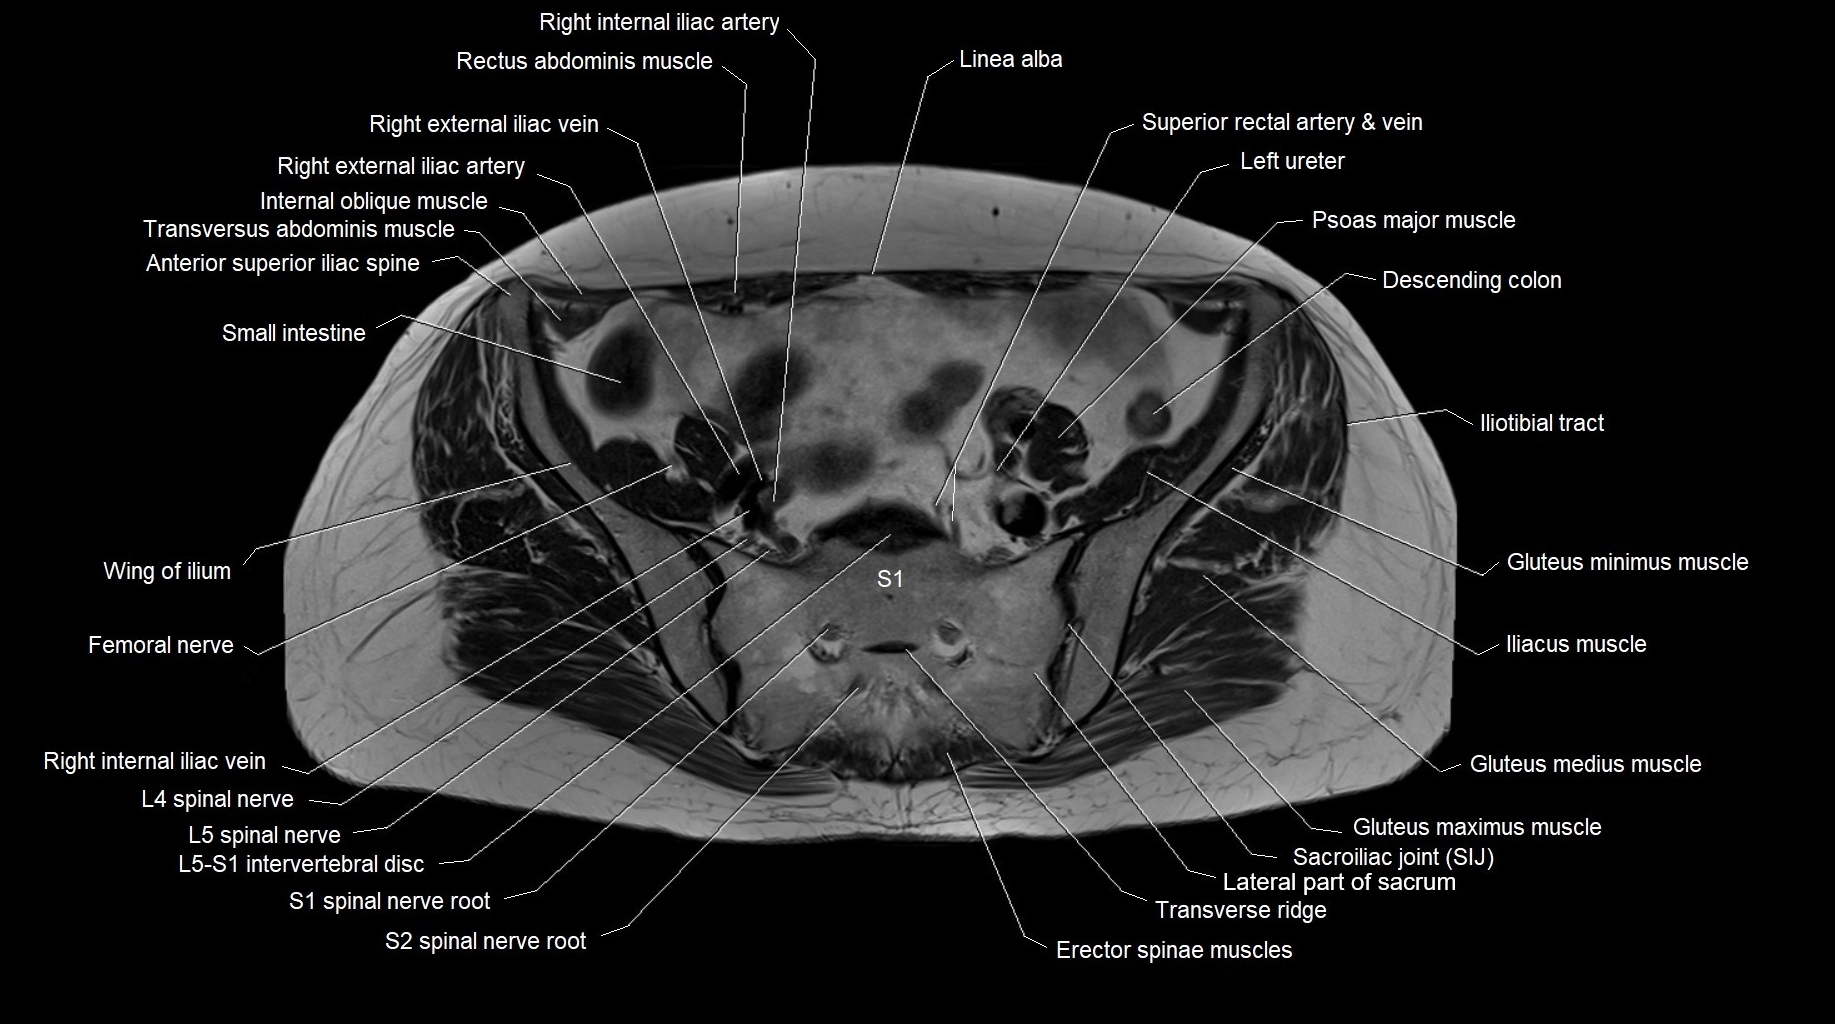

MRI images